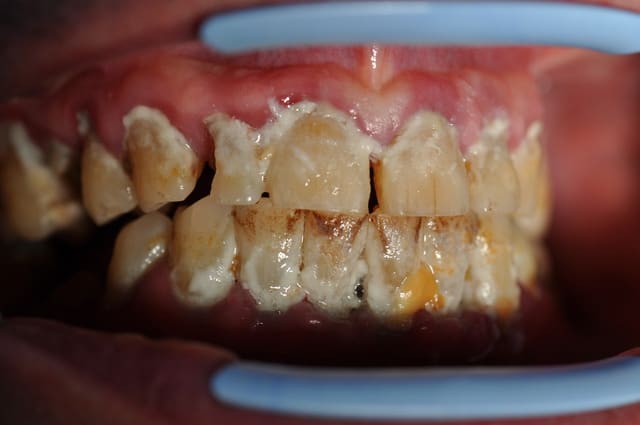

55 ans, infarctus, pontage, stens

et toujours 20 clopes par jour